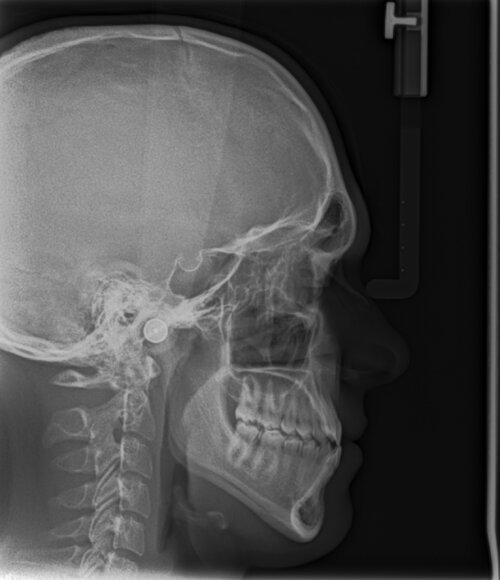

Look at my cephal

Attachments

• H1.jpg

H1.jpg

344.8 KB · Views: 0

Looks fine to me although your bite Is obviously not horizontal

If you were to do bimax, you would get CCW but imo you don't need bimax

CCW can't fix gonial angle, the cut is anterior of gonion

Only implants can fix gonial angle and ramus length (and high cut bsso but that's not done anymore basically)